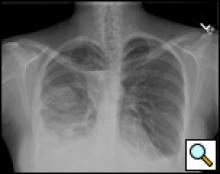

| Figure 1: Presentation chest x-ray revealing bilateral pleural effusions. |

A 35-year old woman undergoing in vitro fertilization noted progressive shortness of breath, orthopnea, and moderate right lower chest discomfort worsening with deep inspiration. She subsequently presented to her gynecologist where ultrasound evaluation revealed ascites and bilateral pleural effusions (Figure 1). She was admitted for management of ovarian hyperstimulation syndrome. A contrast chest CT scan showed massive bilateral pleural effusions, loculated on the right with a small right pneumothorax. Bilateral thoracenteses were performed with drainage of 1300cc of serosanguinous fluid on the left and minimal fluid on the right.